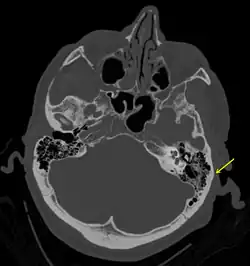

A subtle temporal bone fracture as seen on a CT scan

A basilar skull fracture as seen on CT